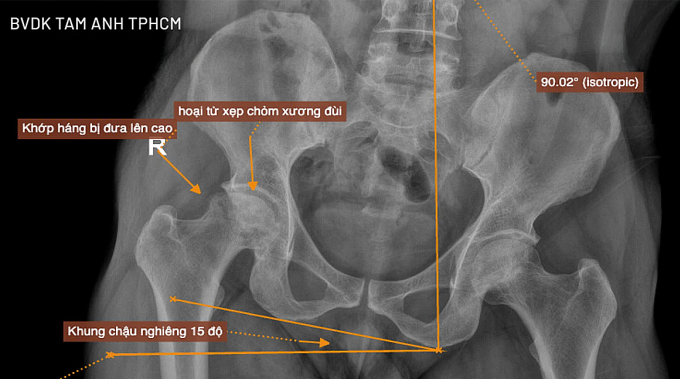

Kết quả chụp X-quang tại Bệnh viện Đa khoa Tâm Anh TP HCM cho thấy ông Hưng bị hoại tử chỏm xương đùi giai đoạn cuối, chỏm xương đùi xẹp và biến dạng, ổ cối thoái hóa một phần, xương chậu nghiêng 15 độ, khi quan sát bằng mắt thường chân phải ngắn hơn chân trái khá nhiều.